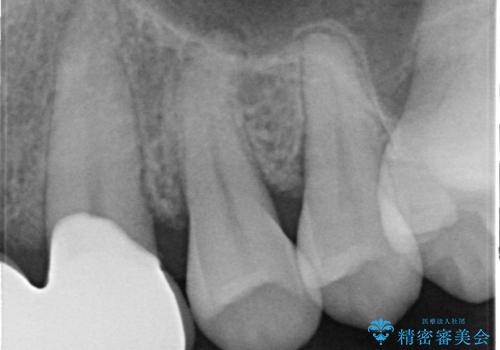

- 前歯部のすきっぱと歯並びが気になるので診て欲しいといらっしゃった方の症例です。

全顎矯正は御希望されなかったため、上顎前歯部のみの部分矯正とオールセラミッククラウンによる補綴を行いました。

今回用いたオールセラミッククラウンはジルコニアフレームという白い素材の上にセラミックを盛っているため、審美性が非常に高いのが特徴です。

また、ジルコニアは人工ダイヤモンドの材料にも使われているほど高い強度を持っており、そのためオールセラミッククラウンは審美性だけでなく、奥歯やブリッジの補綴も可能とするクラウンです。